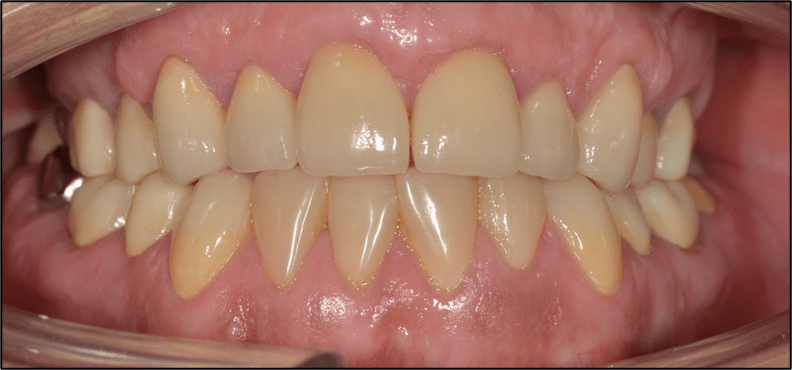

Direct composite is often used to treat toothwear. It is a minimally invasive method that does not damage the underlying tooth structure. It can chip, stain and fail. However, replacement and repair is more straightforward. This case was treated with direct composite alone.